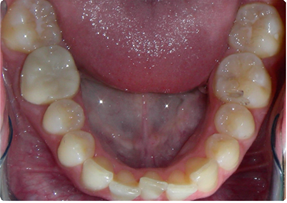

چگونه متوجه می شوید که دندان های شما جابجا شده اند؟

فراتر از نشانه های واضح کج شدن دندان هایتان، شواهدی مبنی بر جابجایی دندان هایتان پس از ارتودنسی می توانند شامل موارد زیر باشند:

• تنگ بودن یا نامناسب بودن نگهدارنده. متخصص ارتودنسی شما نگهدارنده را به صورت سفارشی برای شما می سازد تا کاملاً با دندان های مرتب شما مطابقت داشته باشد. بنابراین، اگر نگهدارنده شما سفت به نظر می رسد یا دیگر مناسب نیست، این نشانه قطعی جابجایی دندان های شما است. متأسفانه، این معمولاً به دلیل استفاده ناکافی از نگهدارنده شما است.

• فاصله بین دندان ها. این یک نشانه شایع و قابل تشخیص است که دندان های شما در حال جابجایی هستند. فاصله ها همچنین ممکن است نشانه ای از مشکلات پریودنتال (لثه) در حال پیشرفت باشند.